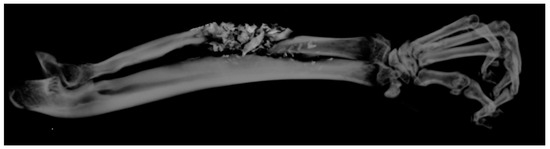

Following the imaging exploration by μCT and 3D image reconstruction through specialized software Vox CT Software Version 3.3.0 r1412, samples were randomly and blindly explored by two experienced medical imaging experts who generated a percentage score for the newly formed callus (Figure 5). Following averaging of the results from the two experts, percentage values for each sample were obtained, as displayed in Figure 4. These individual values were assigned as the total callus volume and were calculated as a percentage of the total volume of the induced bone defect. Selected images from each study group that were examined and evaluated after 3D reconstruction by Vox CT Software Version 3.3.0 r1412 are displayed in Figure 6, Figure 7, Figure 8 and Figure 9.

Figure 8. A 3D μCT image of a sample from the BS group with unstable healing due to sequestered bone replacement fragments, and the entire defect was unable to be healed. These images were assessed for about 30–40% of the bone defect, respectively.